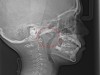

Tonsils and adenoids should be judged against the relative size of the airway rather than the absolute size of the lymphoid tissue46 (Figure 5 and Figure 6). Adenoids are located at the posterior of the nasal cavity on the roof of the nasopharynx (Figure 7). The normal distance from the adenoids to the soft palate for an acceptable airway should be at least 12 mm. For each millimeter decrease, the odds of the child snoring increase 1.61 times. Mouth breathers typically show a smaller upper airway dimension as well.47 The adenoid and tonsillar obstruction creates the trigger, but the deviate facial and neck muscle recruitment and tongue hypotonia cause the maldevelopment.48

(8.) Exam should include nasal anatomy and function. Inferior nasal turbinates occupy the lateral wall of the nose and are easily visualized. When swollen, as in this 12-year-old child, the available airway is reduced and may lead to altered function.

Figure 8